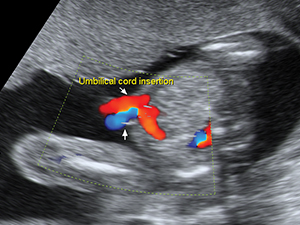

腹部

胎兒肚子之臍帶入口